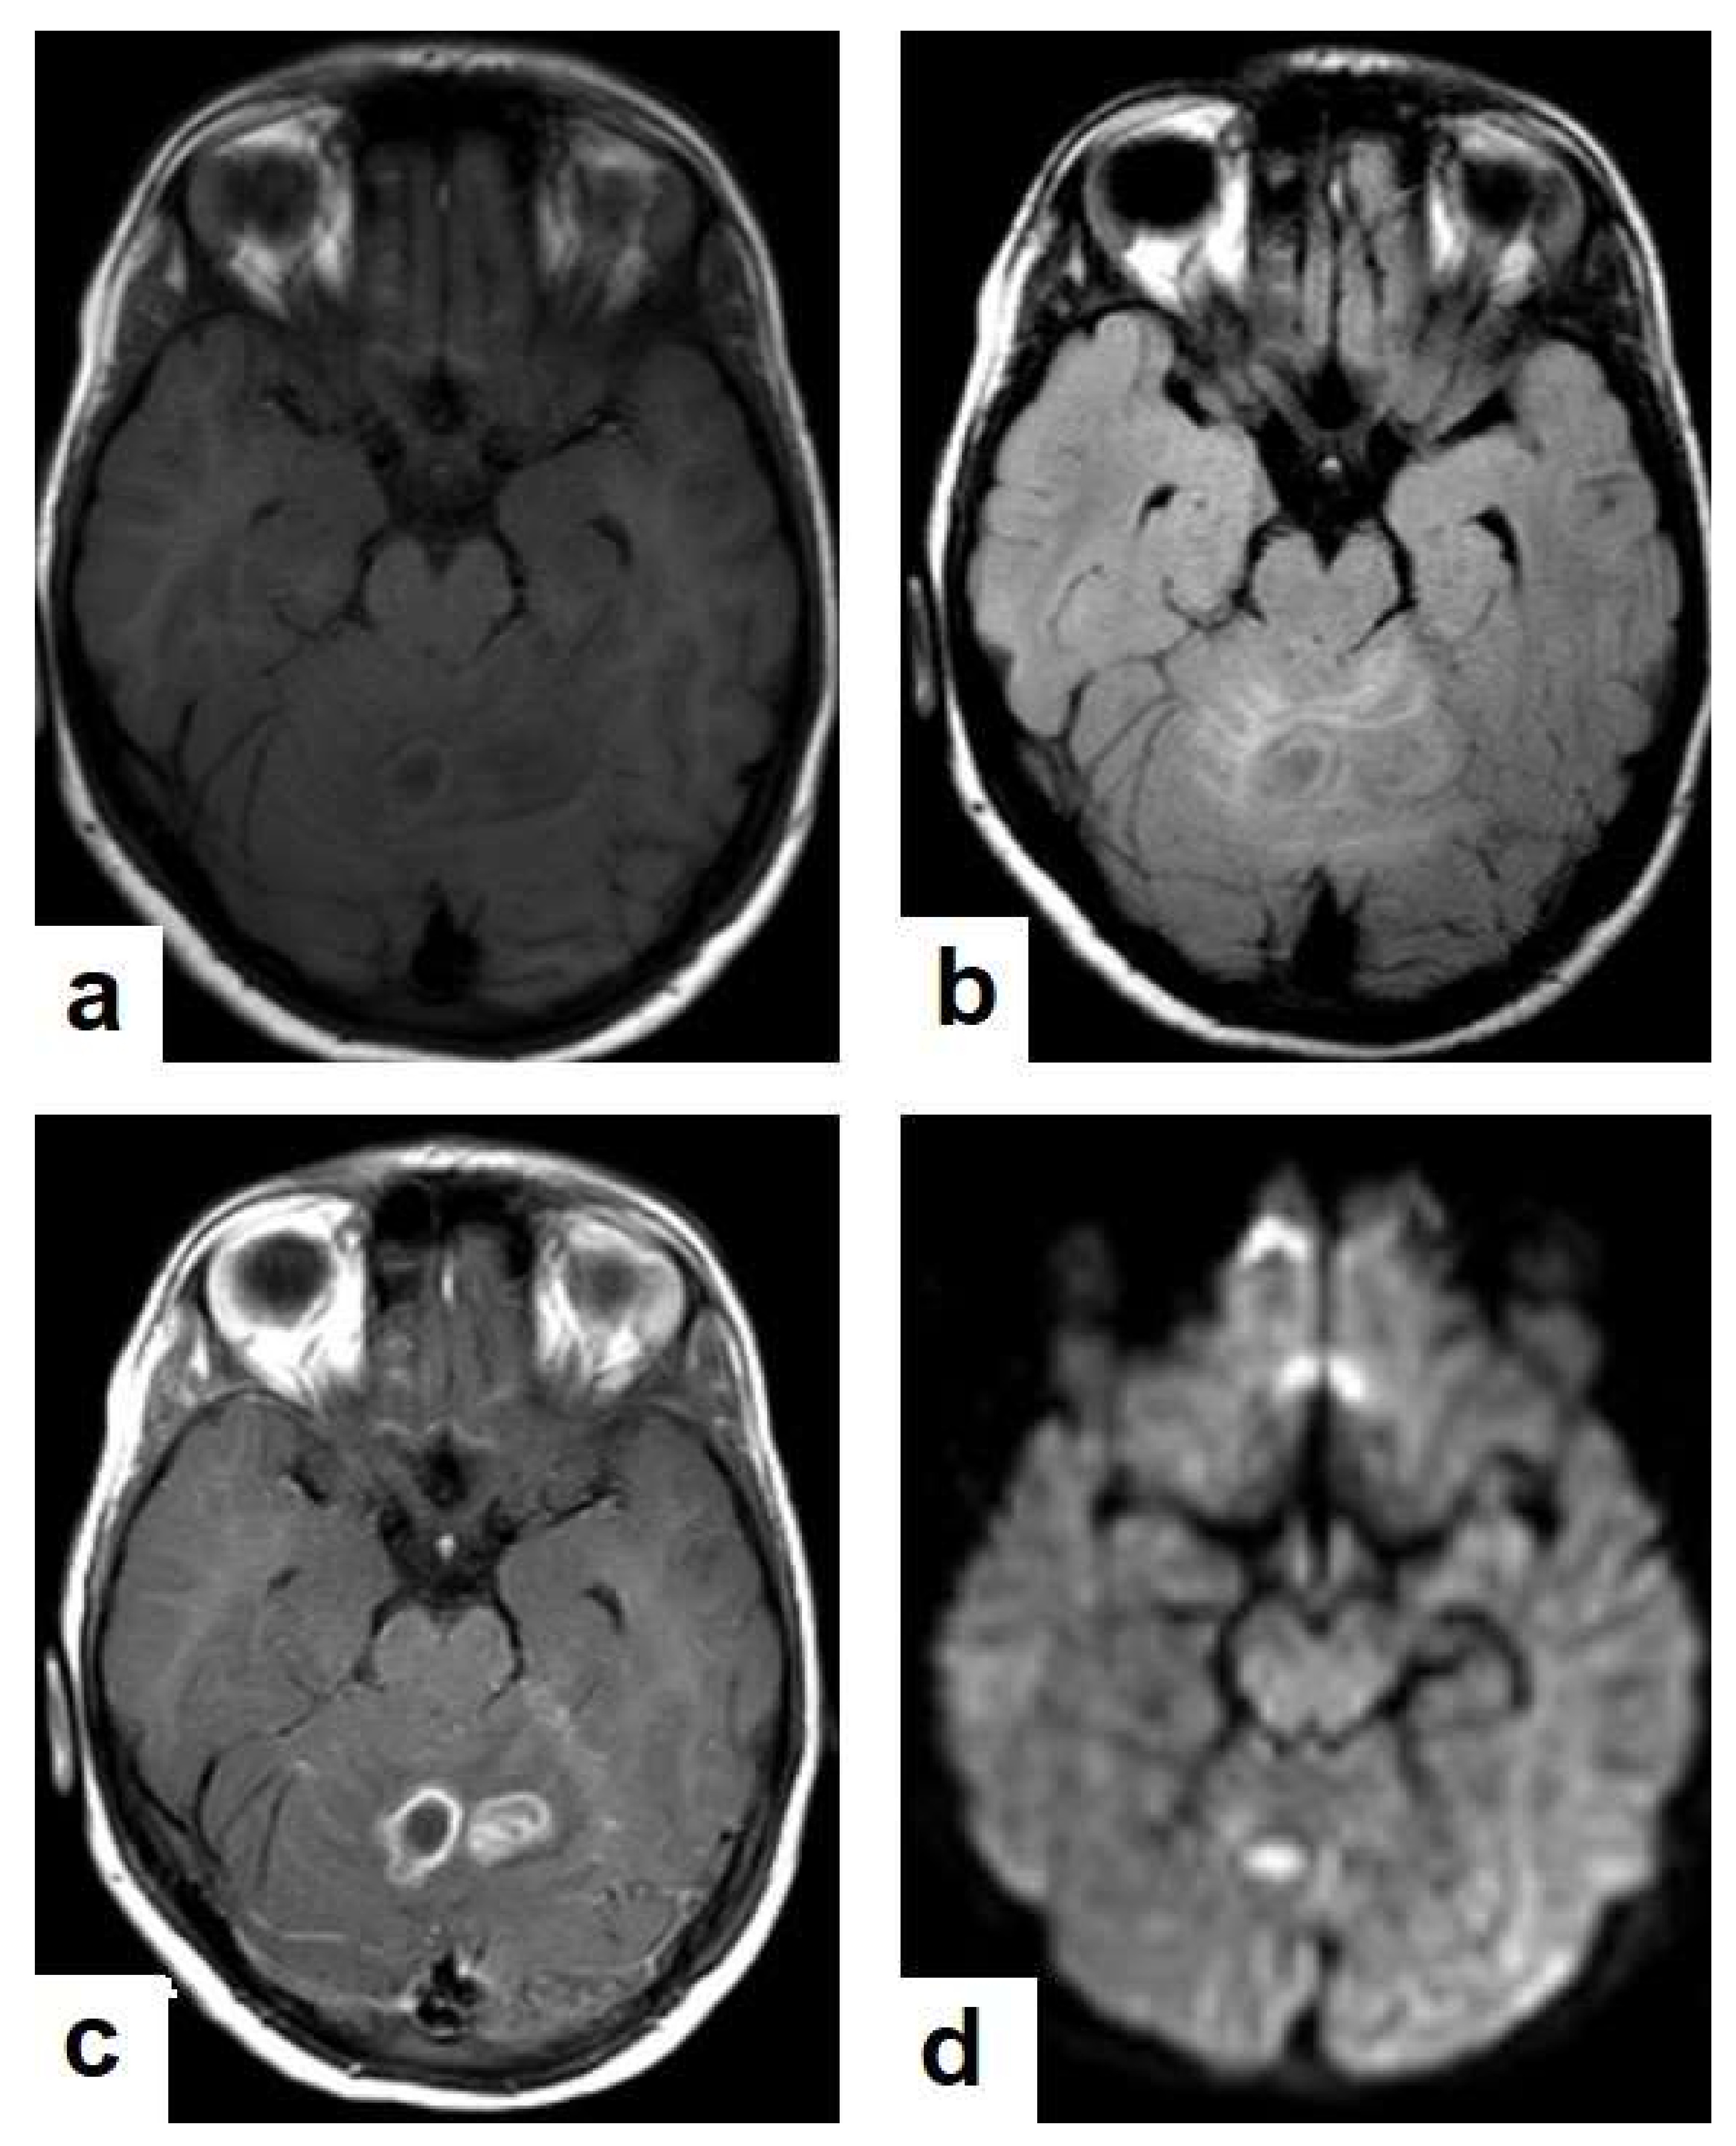

Figure 16. Tuberculous abscess in the right cerebrum of a 13-year-old female. Selected images of brain MRI (a) T1-weighted image (WI), (b) T2-WIs, (c) T1-WI with contrast, and (d) FLAIR-WI. The images show a well-defined lesion in the right cerebral hemisphere with low-signal-intensity content and a high-signal-intensity capsule on T1WI, which appear as high-signal-intensity content and a low-signal-intensity capsule on T2WI (b); there is marginal enhancement on T1WI with contrast administration (c), and there are low-signal-intensity contents and a high-signal-intensity capsule on FLAIR (d). Obvious grade-2 vasogenic oedema around the lesion on T2WI and FLAIR.

• Tuberculous abscesses (Figure 15, Figure 16 and Figure 17) are an infrequent pattern of brain TB, which are present in immunocompromised and elderly patients. They occur either due to the progression of cerebritis or the liquefaction of tuberculoma. On a brain CT, it occurs as a low density area with ring enhancement after contrast administration and the surrounding low density area of edema. On a brain MRI, it appears as a circular or elliptical area of low intensity with ring enhancement after contrast administration and surrounding low intensity area of edema on T1WIs and high intensity area with a high intensity surrounding edema. Tuberculous abscess is a difficult differential diagnosis of a pyogenic abscess, pilocystic astrocytoma, and other cystic lesions. MR spectroscopy may help in differentiating tuberculous from a pyogenic abscess [27,33].